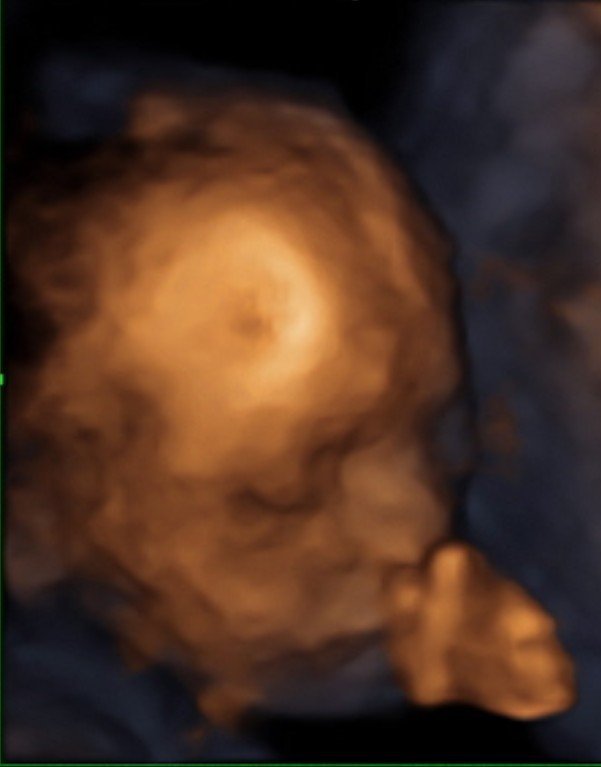

Днес вече съм 27ма седмица и според апликацията на телефона влизам в третия триместър, не мога да повярвам, някак изведнъж дойде